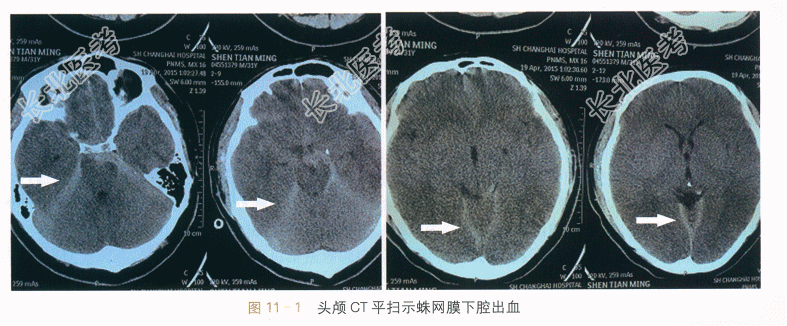

(2)影像学检查:头颅CT示蛛网膜下腔出血,如图11-1所示。DSA示蛛网膜下腔出血,前交通动脉瘤,如图11-2所示。